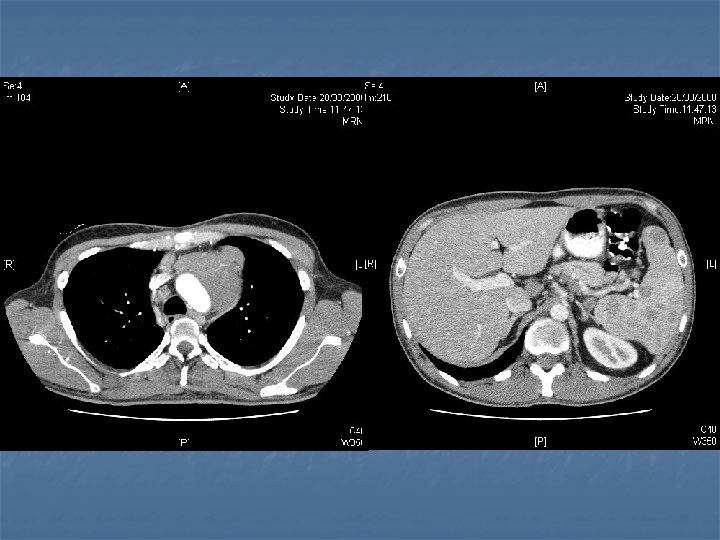

n n n PRETREATMENT INVESTIGATIONS: FBC, Renal and liver function, LDH, urate, Ig. GS. Histology review. Marrow aspirate+trephine (cytogenetics, immunology) CD 4 , HIV viral load. CT Scans. (MR Brain) (PET scan ) Echo / LVEF CMV, Hep B+C, Toxoplasma serology MAI screen. LP for CSF cytology +/- intrathecal Rx. (DLBC , Burkitt, Plasmablastic).